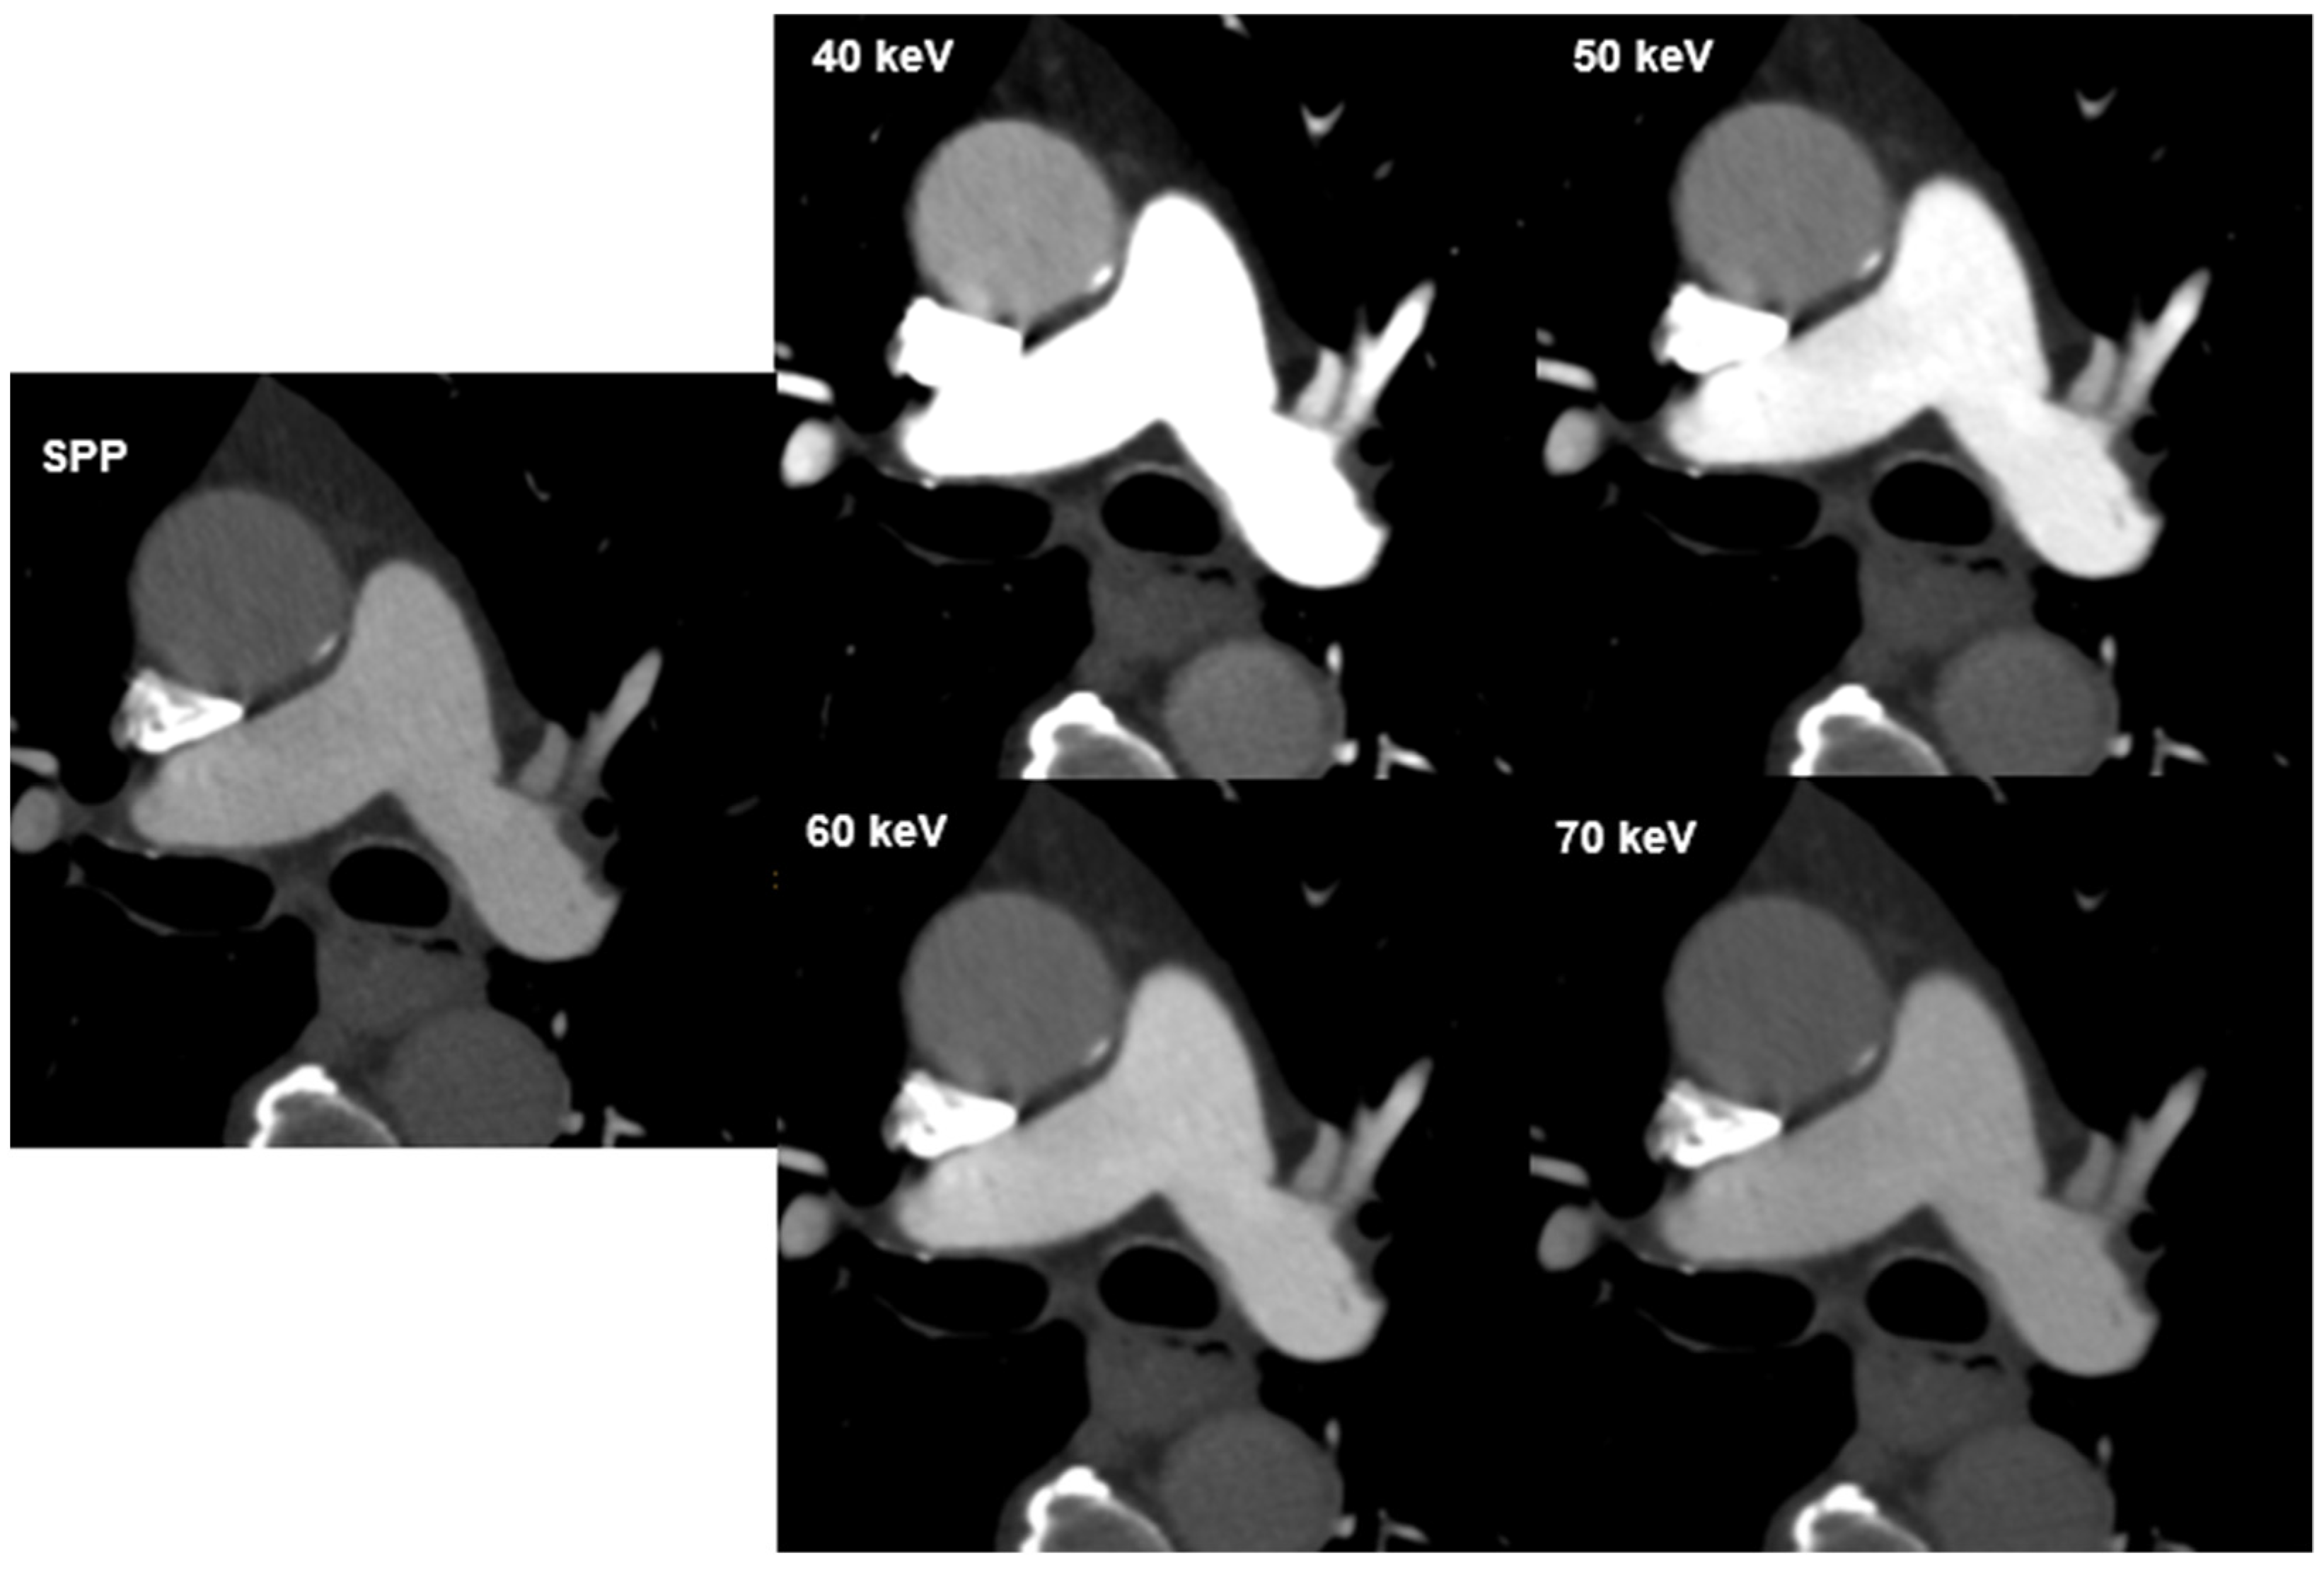

| Imaging Parameter | SPP | 40 keV | 50 keV | 60 keV | 70 keV |

| Image noise median CI95% [range] | 20.85 [19.5–21.80] | 27.25 [25.80–29.85] | 21.70 [20.60–22.70] | 17.65 [17.25–19.00] | 15.60 [14.30–16.45] |

| Signal median CI95% [range] | 358.83 [340.67–393.66] | 1053.50 [976.01–1146.33] | 703.16 [655.36–748.00] | 488.33 [459.67–536.33] | 358.83 [341.00–394.65] |

| SNR median CI95% [range] | 17.78 [14.29–20.13] | 37.56 [32.48–40.48] | 33.18 [27.83–35.08] | 28.06 [23.60–30.78] | 23.61 [19.84–27.04] |